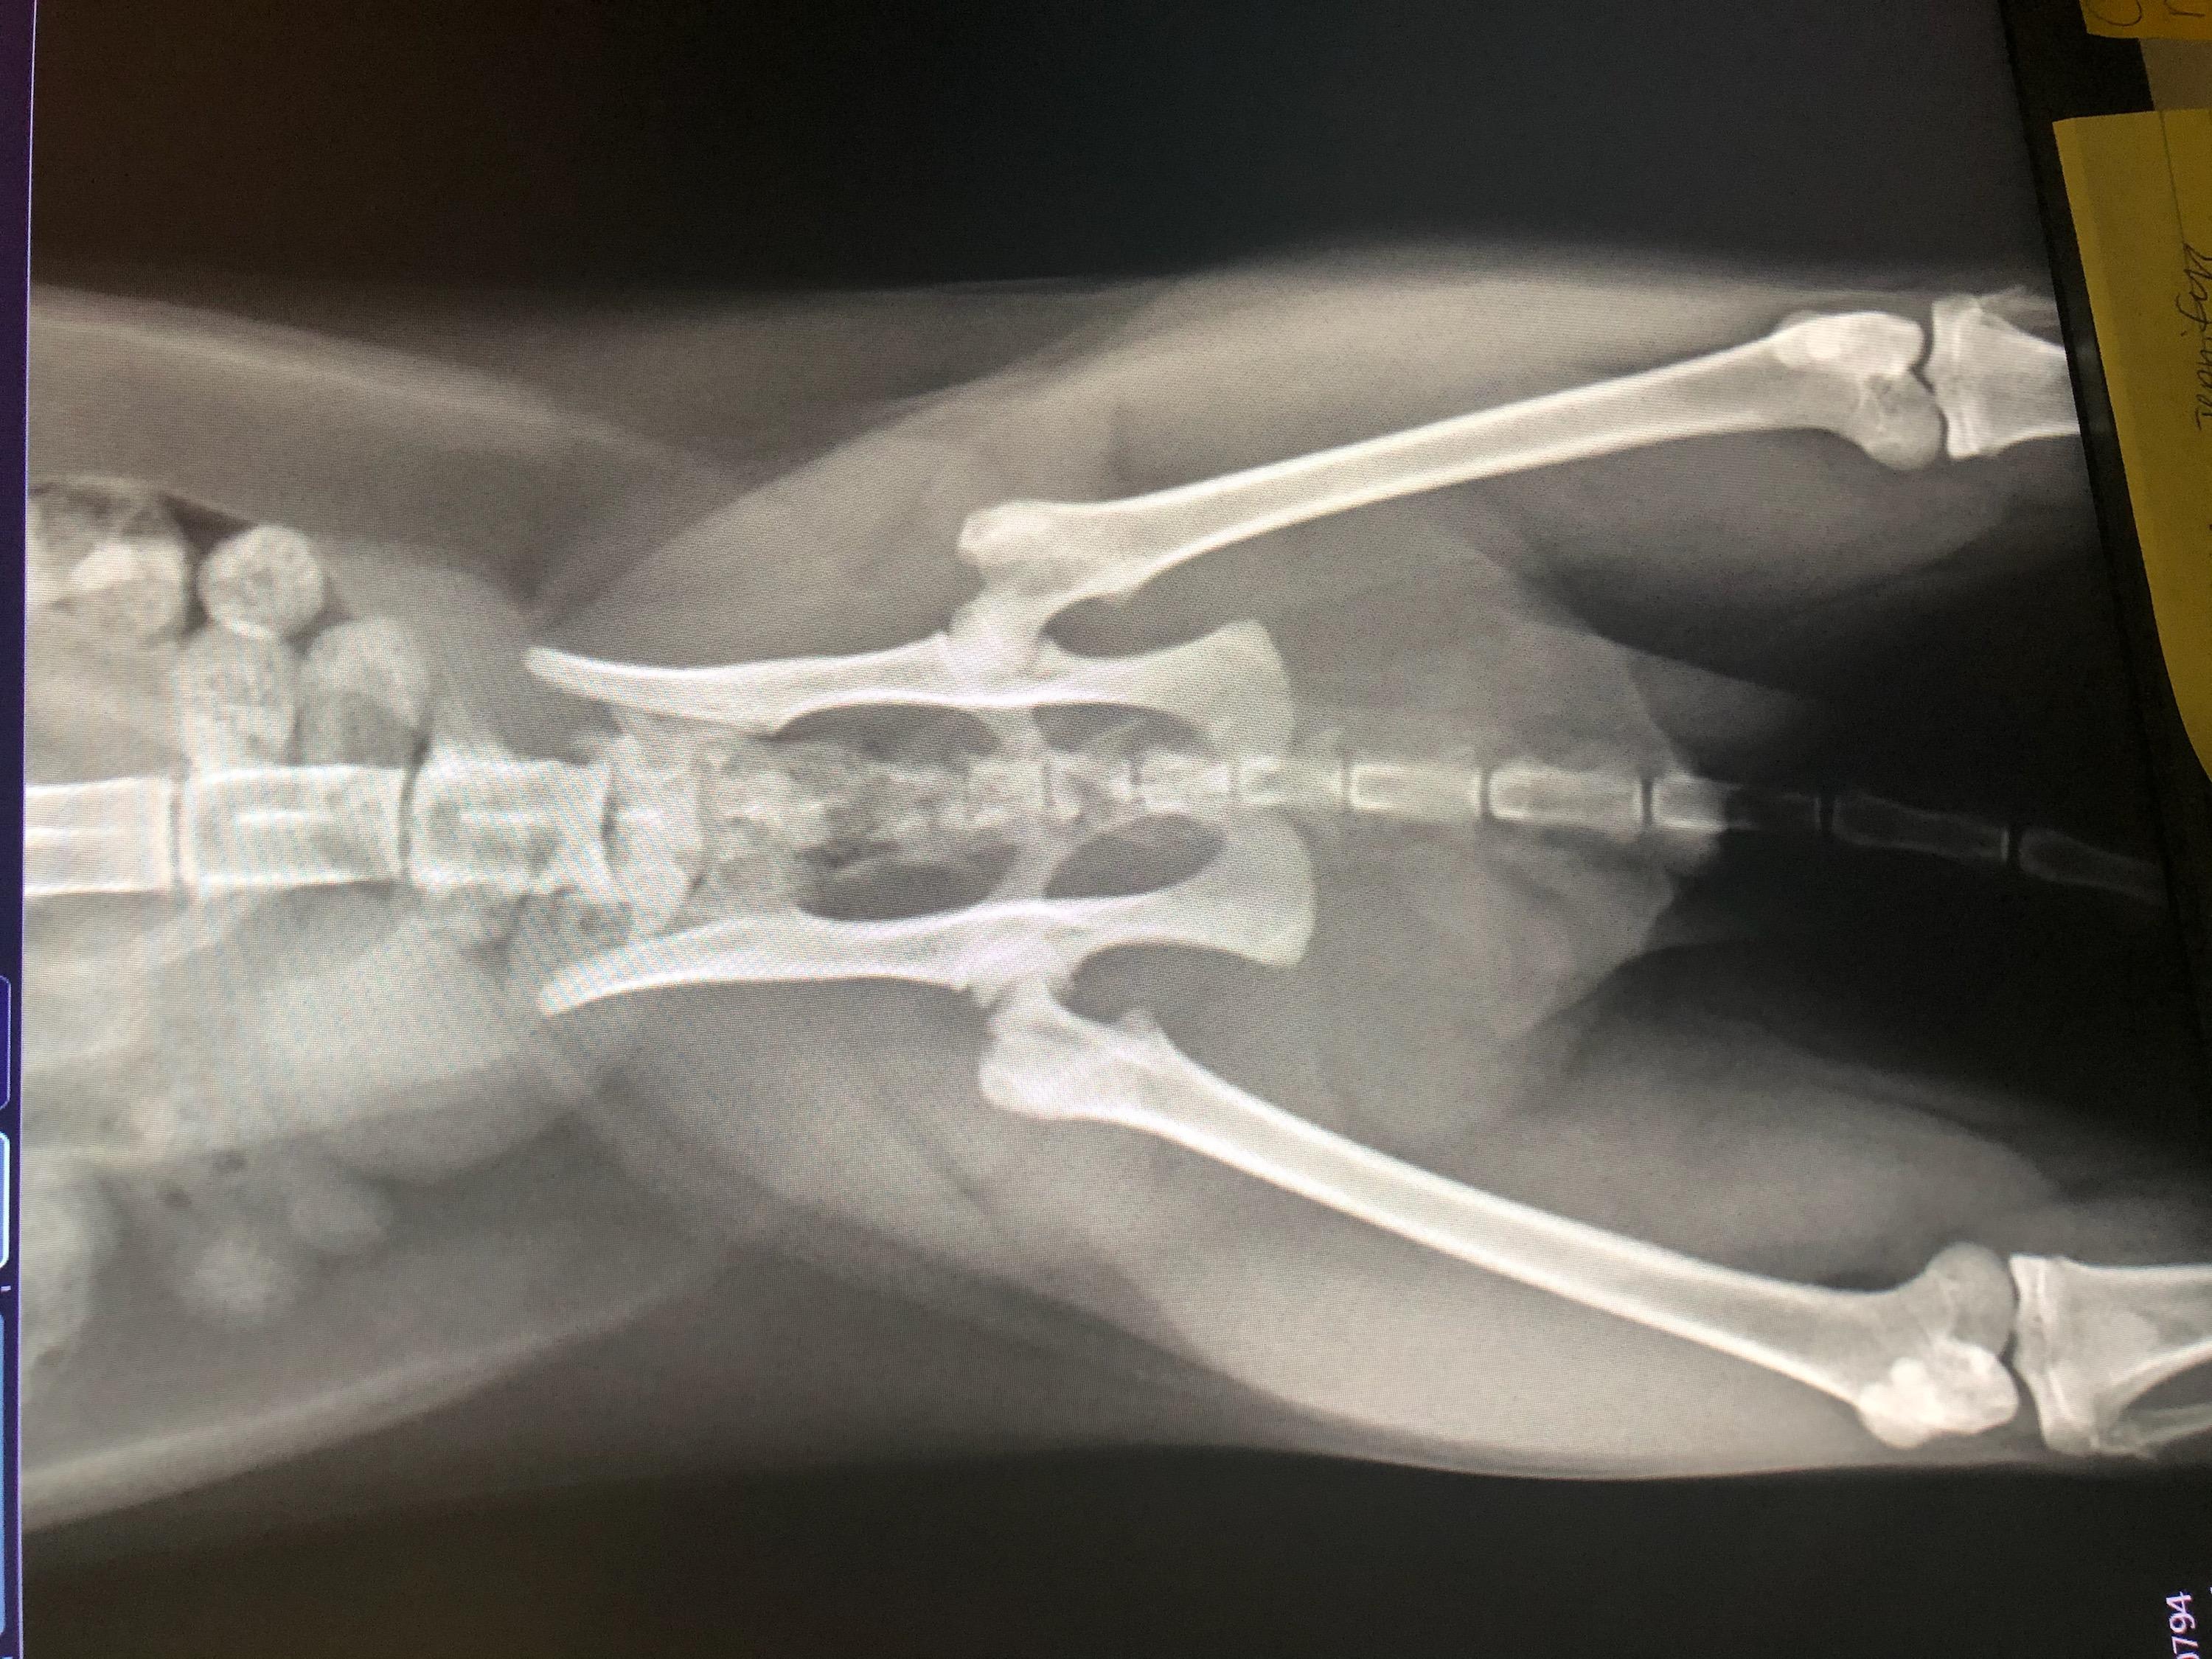

Our cat has been limping for days we took him for X-rays and they want him to see an orthopedic surgeon. Is there anyway you can tell me what is wrong and what the estimated cost or what the procedure would be?

How old is he? If he is past 1 year old, I would be concerned that he may have a fracture of the tibial crest. That is the large bone below the knee. The hips also don't look 100% normal. Without doing an exam on him myself and knowing exactly where he is painful, it is difficult for me to just look at the radiographs and give you a diagnosis. Also, every veterinary surgeon charges differently for different procedures and it is also very depending on location and cost of living. My advice to you would be to go in for the consultation with the surgeon so they can give you more details on what is wrong with him and the best course of treatment. Be sure to ask for estimates for the procedure and if you cannot afford what they are recommending, simply ask what the next best, more affordable option would be. Cats are quite resilient and sometimes they can heal with strict confinement, but I would see what the surgeon thinks. I hope this helps and he starts to feel better soon.